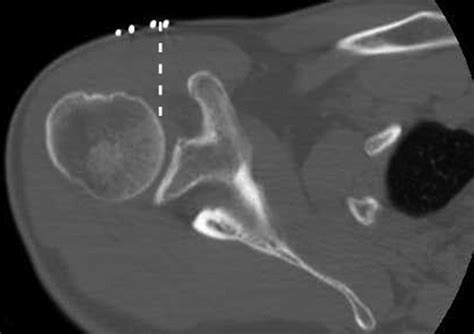

Accurately diagnosing conditions affecting the rotator cuff interval requires a combination of physical examination and advanced imaging. Physicians typically begin with clinical tests to isolate the function of the biceps tendon and the rotator cuff muscles. However, because the interval is deep, imaging is vital for a definitive diagnosis.

Magnetic Resonance Imaging (MRI) The gold standard for visualizing soft tissue, ligamentous thickening, and interval tears.